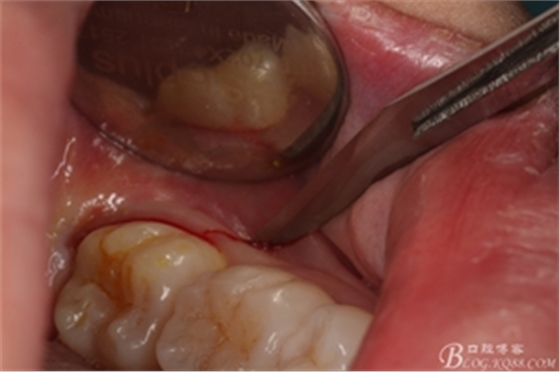

圖6.麻醉效果確定后,在37的近中做垂直松弛切口+遠(yuǎn)中水平切口

圖7. 遠(yuǎn)中的水平切口